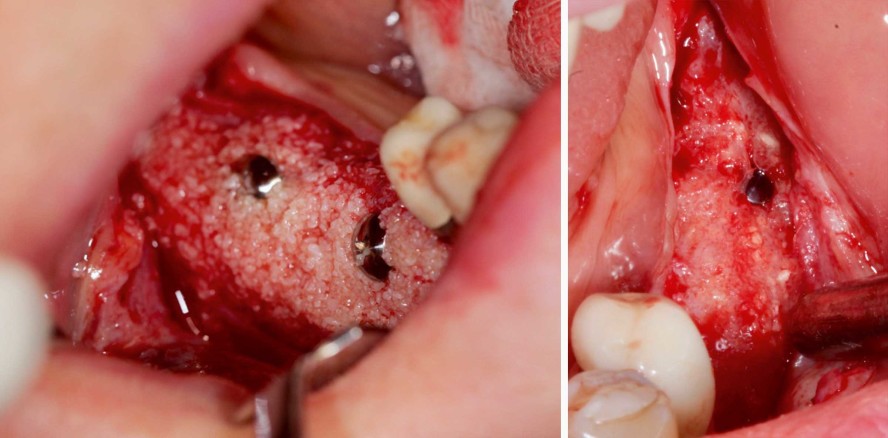

Schritt eins: Kieferkammaugmentation

Die Patientin wurde perioperativ mit Azythromycin (500 mg/Tag) für drei Tage antibiotisch abgedeckt. Zunächst wurde der Patientin chairside venöses Blut abgenommen, das anschließend zu autologem Blutkonzentrat aufbereitet wurde (PRF-System nach Choukroun; Platelet Rich Fibrin). Nach erfolgter Lokalanästhesie wurde dann im linken Seitenzahnbereich ein Mukoperiostlappen präpariert. Zur räumlichen Stabilisierung des partikulären Knochenaugmentats wurden zwei Schirmschrauben im Sinne der Umbrella-Technik nach Dr. Dr. Markus Schlee inseriert (Abb. 3) und Sticky Bone, angemischt aus PRF und porcinem Knochenersatzmaterial (Apatos, OsteoBiol), in den Defekt eingebracht, um den Kieferkamm vertikal und horizontal zu rekonstruieren. Darüber wurde eine xenogene Bone Lamina porcinen Ursprungs (Cortical Lamina hart, OsteoBiol) gelegt, die wiederum mit einer PRF-Membran aus dem Blutplasma der Patientin abgedeckt wurde. Hiernach wurden Titanpins inseriert, um die Membranen zu stabilisieren. Anschließend erfolgte das Vernähen der Operationsstelle mittels modifizierter Matratzennaht und Einzelknopfnähten.

Das beschriebene Vorgehen wurde für den rechten posterioren Unterkiefer wiederholt (Abb. 4). Zusätzlich wurde in diesem Bereich zur Verdickung der Attached Gingiva ein Tunnel präpariert, in den eine mit Hyaluronsäure (hyaDent BG, Regedent) biologisierte resorbierbare Kollagenmatrix (Fibro-Gide, Geistlich Biomaterials) eingeschoben wurde. Folglich lässt sich in diesem Bereich nach Ausheilung ein Mehr an keratinisierter Gingiva beobachten (Abb. 14).